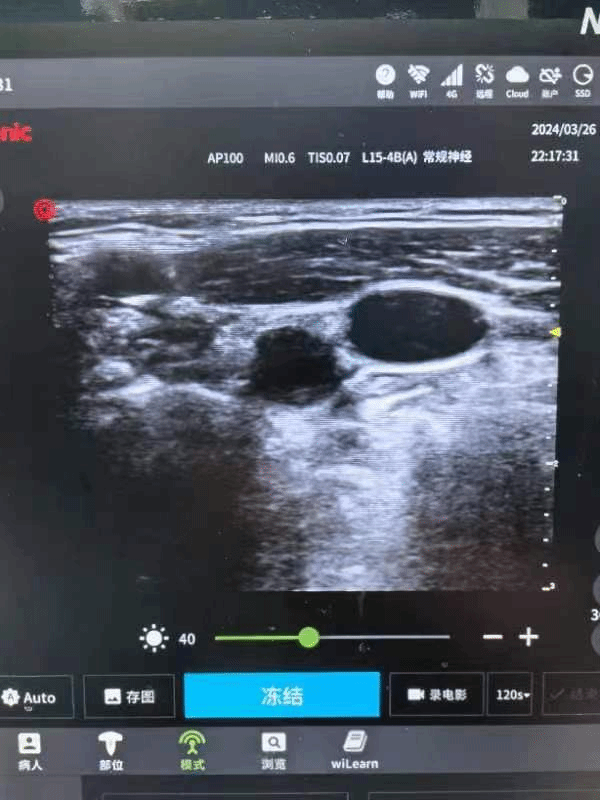

开展的主要特色技术包括:可视化喉镜插管术、纤支镜引导插管术、可视内镜插管术、低温麻醉、控制性降压、麻醉深度监测术、肌松监测术、无创心排监测术、脑氧监测术、术中唤醒术、术中血液回收术、术中血气分析、体外循环心内直视术的麻醉、B超引导下的各种神经阻滞和动静脉穿刺术、漂浮导管插管术、口腔无痛治疗术、无痛人流术、无痛胃肠镜、无痛纤支镜、无痛分娩术、无痛ERCP技术等,开设疼痛门诊、麻醉门诊、日间手术中心和疼痛病房(编制床位55张)等。